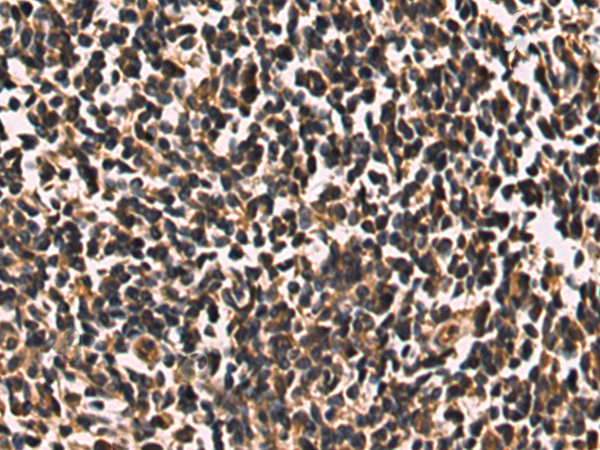

分类: 科研抗体货号: P06435别名:应用: WB,IHC反应种属: Human, Mouse